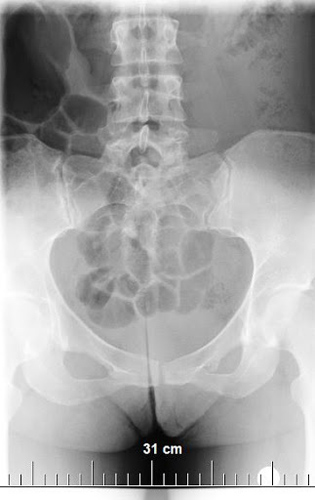

Клинические признаки вывиха копчика не всегда достаточны для постановки диагноза, так как они напоминают ушиб. Для определения вывиха или подвывиха используется визуализирующая диагностика.

Для точного определения травмы проводят цифровой рентген. Более информативными являются магнитно-резонансная или компьютерная томография, но они доступны не во всех поликлиниках, требуют больше времени и стоят дороже. Поэтому чаще всего при первичном осмотре после травмы делают рентген. Остальные виды диагностики (МРТ или КТ) назначаются позже, если рентген не дал точных данных или в процессе лечения, когда нет срочности.

Ушиб копчика со смещением позвонков фиксируется рентгенографией. Если произошло падение, удар, ДТП или неудачное движение, необходимо незамедлительно обратиться к травматологу для обследования. Это поможет исключить загиб с деформацией копчиково-крестцового сустава, а также трещину или перелом.

Для диагностики необходимо обратиться к врачу-вертебрологу или травматологу (в случае травмы позвоночника). Врач назначит рентгенографию в разных проекциях для оценки состояния рудиментарного отдела позвоночника. При необходимости также могут быть назначены УЗИ, МРТ и КТ.